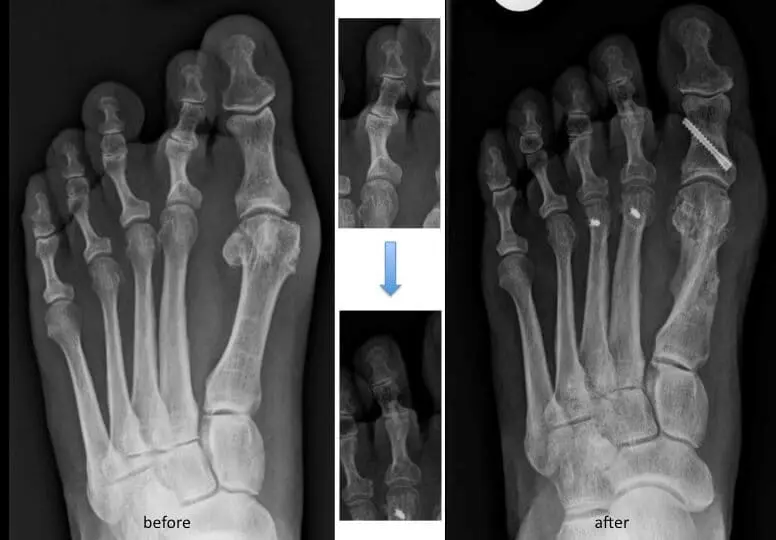

Résection d’un conflit douloureux et saillant (arthroplastie interphalangien)

Fixation de l’articulation douloureuse avec une certaine angulation (arthrodèse)

Ostéotomie de la phalange ou du métatarsien

Exceptionnellement, une broche est mise en place et sera enlevée vers la 4ème semaine en consultation. Cette ablation n’est pas douloureuse et est à comparer à une prise de sang. En fonction de la chirurgie, le traitement postopératoire comporte l’appui immédiat sur une chaussure postopératoire adaptée durant 4 semaines ou un appui différé.